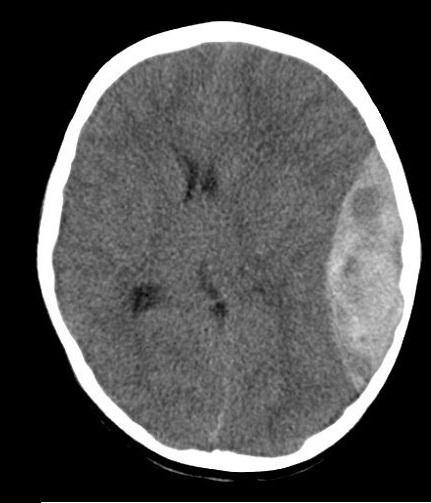

Acute Subdural

Acute Subdural 2